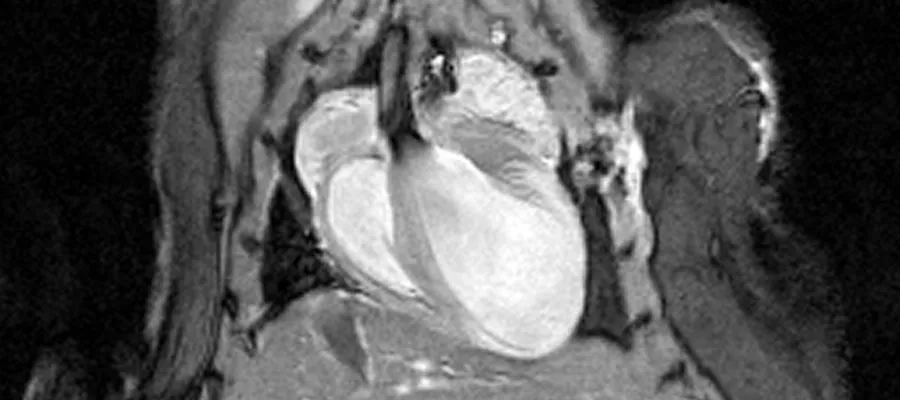

short-axis view MRI of mouse heart

short-axis view

By synchronising rapid imaging with the cardiac cycle it is possible to generate “movie” sequences from which information can be obtained about the function of the heart. Images can be acquired in any orientation, but usually they are acquired in the short-axis, 2- and 4-chamber views. Standard cardiological parameters such as left ventricular volume, ejection fraction and cardiac output can be determined. Contrast agents enable the progression of myocardial infarcts to be monitored in longitudinal studies.

A Gadolinium contrast agent can be used to measure infarct size (pale grey myocardium). Images at twelve different phases of the cardiac cycle are acquired in approximately 3 minutes (Images courtesy of Jansen lab and Gray lab).